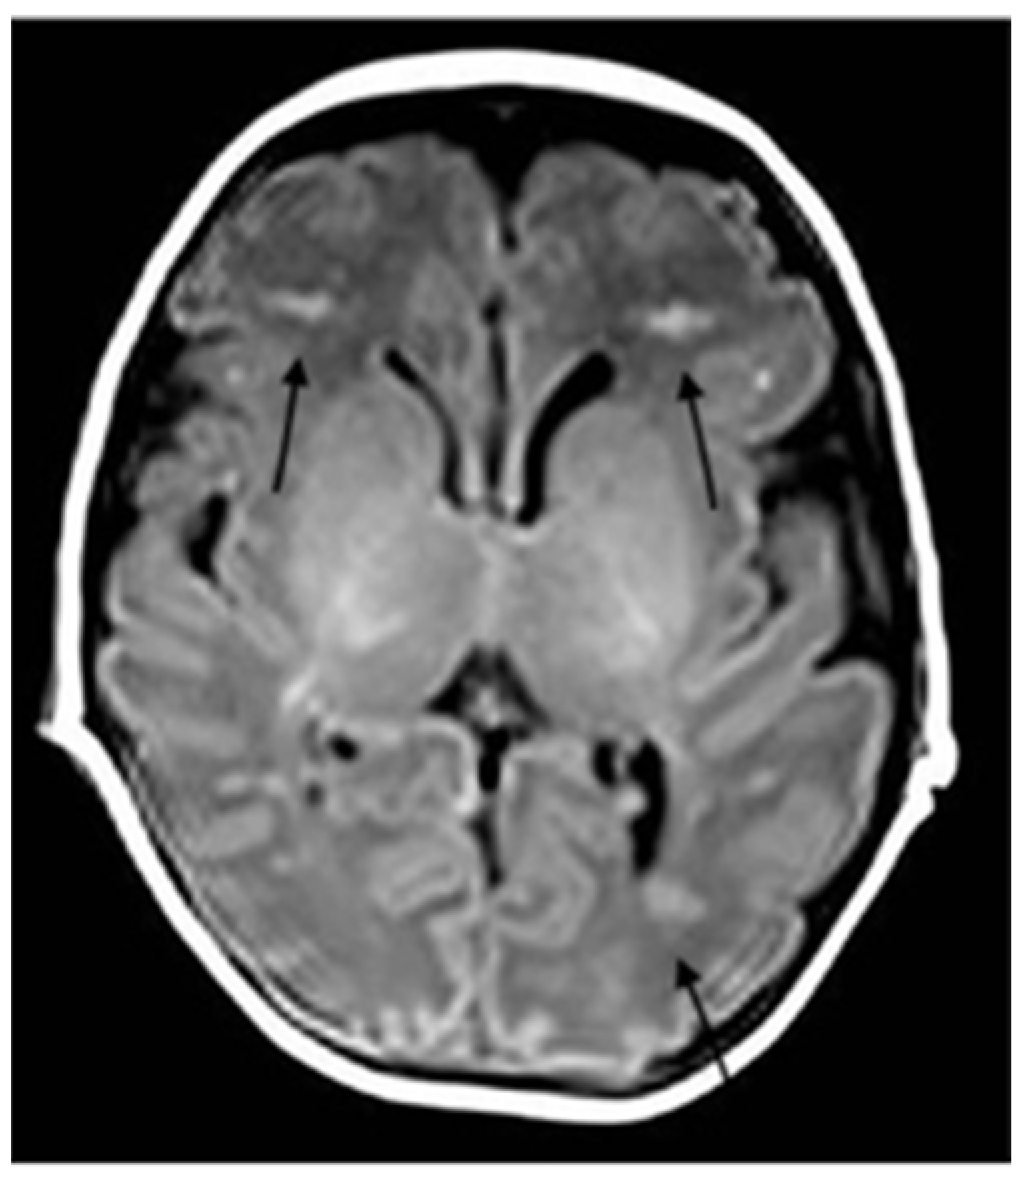

2. Case Description